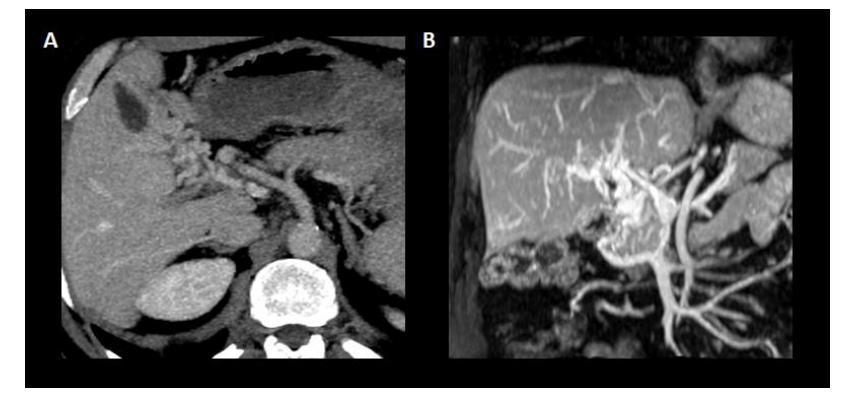

关于门静脉血栓的“年龄”,近期门静脉血栓的特征包括低回声和低密度血栓,门静脉平扫时门静脉密度增加,门静脉密度增加,增强CT扫描中心透明。相关的肝脏血流灌注改变也可以表现为动脉期肝实质增强,门脉期增强减弱。相反,血栓壁内的钙化和海绵状肿瘤的存在提示慢性(图3)。必须指出的是,前者只能用US或CT发现,而不能用MR检查,而且在PVT发病后1-3周内可发生海绵状改变(图4)。

图4.门静脉海绵样变。(A)显示门静脉主干被起源于门静脉血管的门静脉侧支取代的轴位平面。(B)门静脉的冠状面及其海绵样变与构成门静脉侧支的新血管的缠绕。